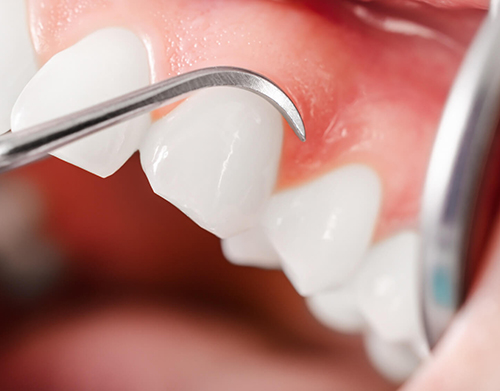

Lamİnate Veneer (Yaprak Porselen)

Yaprak porselen olarak da bilinen laminate veneer uygulaması, adını kullanılan takma tırnak kalınlığındaki plakalardan alır. Bu yöntem, dişlerin daha beyaz görünmesini ve diş bozukluklarının ortadan kaldırılmasını sağlar.

Dişlere doğal bir beyazlık kazandıran laminate veneer uygulamasında öncelikle kişinin diş yapısı incelenir. Ardından diş yüzeyinden çok ince bir tabaka alınarak veya dişlerin durumuna bağlı olarak hiç alınmayarak yerine hazırlanılmış olan laminate veneer’lar yerleştirilir ve yapıştırılır. Bu işlem esnasında özel bir yapıştırıcı malzeme kullanıldığından lamine veneer’ların düşmesi veya diş yüzeyinden ayrılması mümkün değildir.